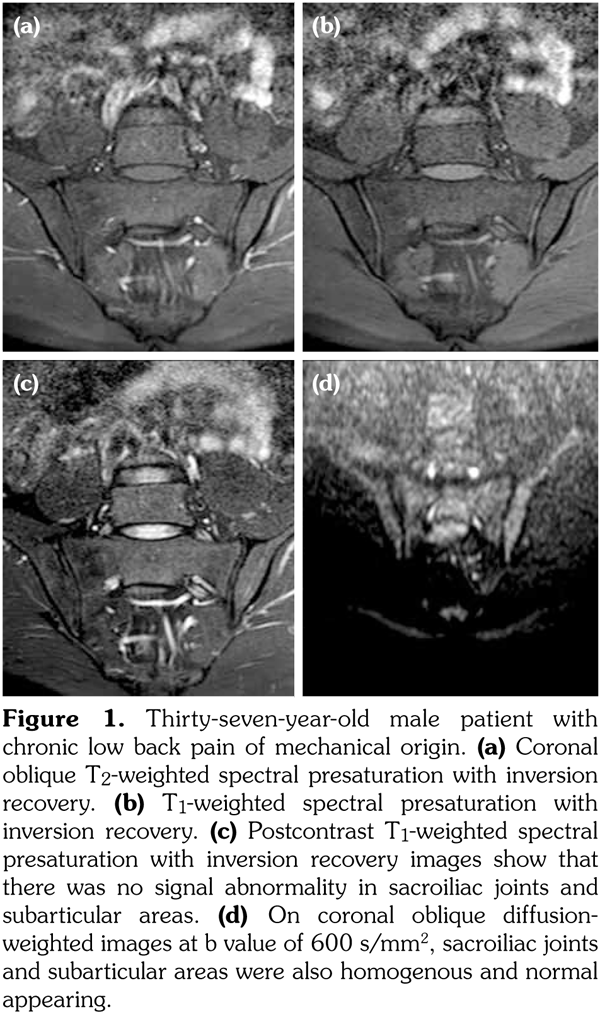

Sacroiliac joints were assessed according to ankylosing spondylitis criteria. Before evaluation of standard MRI protocol, patients’ information was removed from images. Afterwards, two experienced radiologists evaluated the images for the presence of inflammatory activity twice at separate sessions to assess interobserver variability. Following the examination of T2-weighted SPIR, contrast- enhanced T1-weighted SPIR, and DWIs at b values of 600 s/mm2, two radiologists and rheumatologists reached a consensus on the disease activity in the light of positive features of Berlin criteria. The DWIs were transferred to a separate workstation (Phillips, Extended MR workspace, 2.6.3.2.HF3, Netherlands). ADC maps were generated. T2-weighted SPIR images, contrast-enhanced images and diffusion-weighted images with ADC maps were put on the screen side by side. In the disease group, the hyperintense lesions on T2-weighted SPIR images and enhanced focuses on contrast- enhanced images were noted and the same lesions were marked on DWI images and ADC map. A circular ROI with a range of 40-75 mm2 was placed in those areas. In the control group a circular ROI was placed in the subarticular area of joints. Also, the same process was performed for the normal-appearing bone marrow areas near the joints of the disease group (Figure 2). Four standard measurements were conducted from each joint, including two on sacral and the other two on the iliac side for all patients (Figure 3). Additionally, two measurements were conducted from the fifth lumbar vertebra and one from each iliac wing (Figure 4). All measurements were performed twice. ADC values were expressed as square millimeters per second. The r-ADC ratio was calculated by dividing ADC value of subchondral bone or inflammatory lesions to ADC values of the fifth lumbar vertebra and iliac wings.